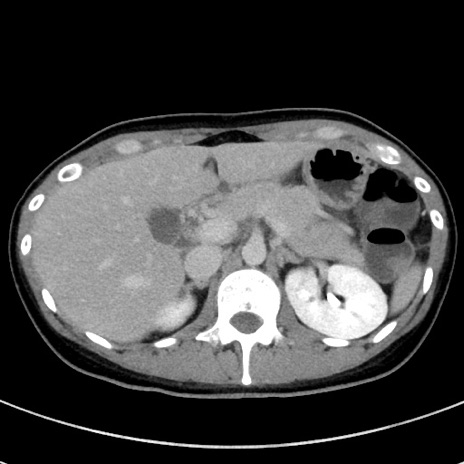

症例17(横断像)

【症例】20歳代女性

【主訴】嘔吐、下腹部痛

【現病歴】昨日夕食後に嘔吐し下腹部痛が出現。本日になっても嘔吐持続し改善しないため来院。

【身体所見】意識清明、BT 37.2℃、BP 108/67mmHg、腹部:平坦、やや硬、下腹部正中から右にかけて圧痛あり、反跳痛軽度あり、tapping pain(+)。

【データ】WBC 13600、CRP 14.94